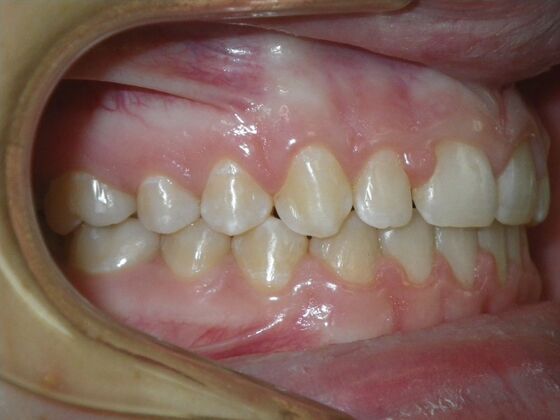

Patient presents desiring all spaces on upper and lower teeth closed. She will need slight expansion of upper arch due to lower molars leaning inward toward tongue. Used nitanium palatal expander with built in rotation of upper molars and lower lip bumper to upright lower first molars. Patient was also informed that her upper lateral incisors would require bonding due to their small size to close all space.